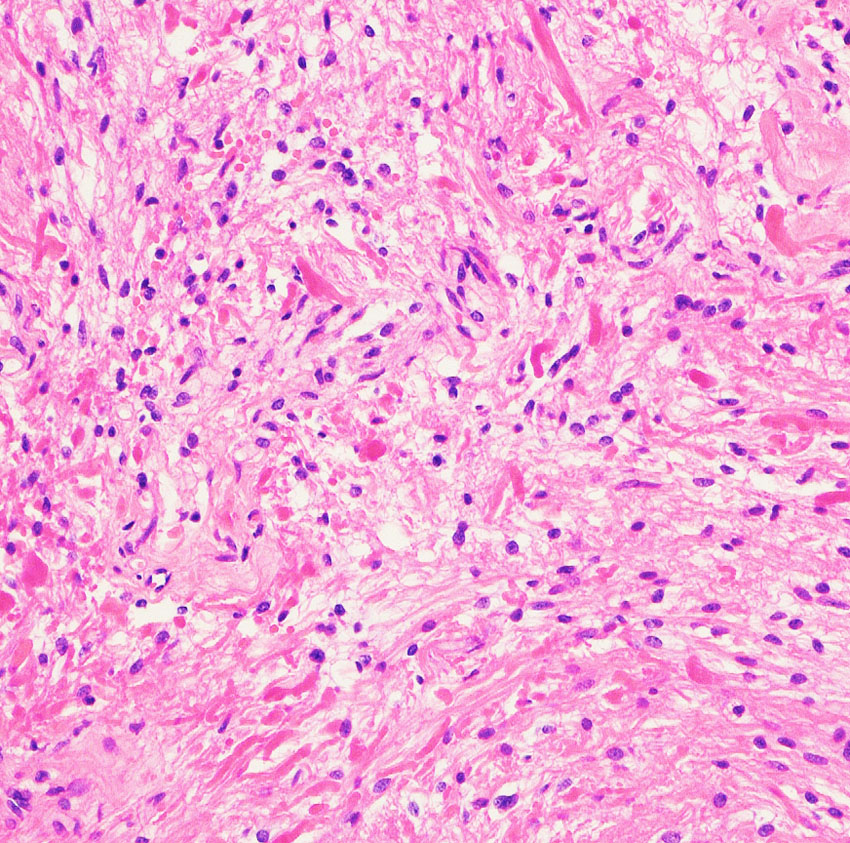

- 病理は,小さい子どもでは毛様粘液性星細胞腫 グレード1 pilomyxoid astrocytoma です

- 年長さんから思春期は,毛様細胞性星細胞腫 グレード1 pilocytic astrocytomadです

乳幼児時期には,病理組織像が毛様粘液性星細胞腫で,MRI T2で均一な高信号になりガドリニウムで強く増強されます。腫瘍の増大速度は速く,稀には髄液播種することもありそれが腫瘍死の原因となることもあります。奏効率の高い化学療法を早く開始する必要があります。

少し経過して幼児期には,速度は落ちるがやはり腫瘍は増大傾向をたどり腫瘍内のう胞形成とのう胞の拡大をみることが多いでしょう。この時期にも症状の悪化が多く,化学療法は継続する必要があります。pilomyxoid typeからjuvenile type pilocytic astrocytomaへ病理組織像が変わっていきます。

病理所見では,幼児型のpilomyxoid astrocytomaの部分が混在します。その部分が増殖と腫瘍増大に関わっています。T2強調画像で高信号でガドリニウム増強される部分です。

myxoidな部分です。右下のMIB-1染色では3%ほどの陽性率であり,数年単位では腫瘍増大があり得ることを示します。柔らかく出血性で吸引摘出できる部分の腫瘍です。IDH wild type, BRAFV600 wild type, H3K27 wild type, FGFR1 N546K mutationでした。

厚く肥厚した視神経鞘の内部の視神経組織はほとんど腫瘍に置き換わっていて,GFAPで染色され高度の石灰化を伴います。これは腫瘍というよりも瘢痕化してしまった,adult-type pilocytic astrocytomaに認められる所見です。

Rosenthal fiber, eosinophyric granular body, psammoma bodyなどが認められ,成熟しきって退行変性に移行するpilocytic astrocytomaの像です。この部分は増大しません。線維性に極めて硬い組織です。